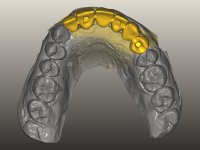

O paciente foi observado conjuntamente e a dúvida que surgiu de imediato foi se seria possível com a regeneração óssea a efectuar poder ser reabilitada naturalmente a zona das papilas interdentárias. Nesse sentido foi feito um enceramento de diagnóstico que contemplaria as duas hipóteses, utilizando ou não a cerâmica gengival. A confecção desse enceramento foi fundamental para expor ao paciente a dificuldade da reabilitação. O wax-up deu origem a um mock-up que foi aprovado pelo paciente e que simultaneamente serviu de guia imagiológica. O caso foi planificado cirurgicamente e realizada uma guia cirúrgica com que foram colocados os implantes. Após 10 semanas foi feita a 1ª impressão para confecção da ponte provisória. Foram criados os primeiros perfis de emergência na gengiva artificial e foi digitalizado o modelo. Por processo de CAD-CAM foi confeccionada uma ponte provisória aparafusada baseada no enceramento de diagnóstico. A ponte trabalhou durante 8 semanas os tecidos moles que foram fielmente copiados numa impressão com técnica de moldeira aberta. Os transferes foram individualizados com resina composta para copiarem fielmente os perfis de emergência criados pela ponte provisória. Confeccionado o modelo de trabalho definitivo, foi realizada uma infra-estrutura em zircónio seguindo a orientação do enceramento de diagnóstico. O assentamento da infra-estrutura foi testado em boca e simultaneamente foi novamente impressionados os tecidos moles com um silicone fluido. Nessa consulta foi feito o levantamento da cor. Os dentes 13 e 23 apresentavam uma saturação anormalmente forte que resolvemos não valorizar, optando por privilegiar a relação com o sector antero-inferior. Foi realizada uma nova gengiva artificial com a impressão que acompanhou a impressão de arrasto com a infra-estrutura. Após a colocação da cerâmica na infra-estrutura foram coladas as meso-estruturas. O trabalho final foi aparafusado lentamente permitindo a adaptação dos tecidos moles.